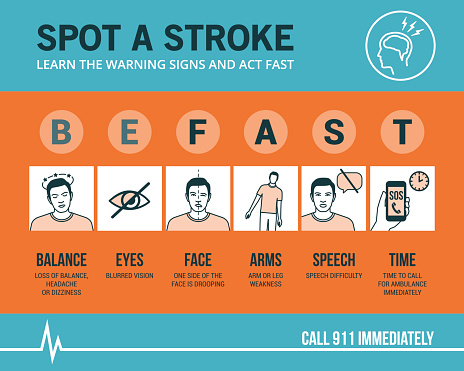

World heart day: Enlarged heart, diabetes and heart disease, fluid around the heart, massive heart attack

September 29th is World Heart Day, which is held and organized by the world heart foundation. The purpose of this occasion is to inform people about cardiovascular diseases, which cause many cases of preventable death in the world. To better facilitate this purpose, we have compiled a list of articles to help get you started ...click here to read more